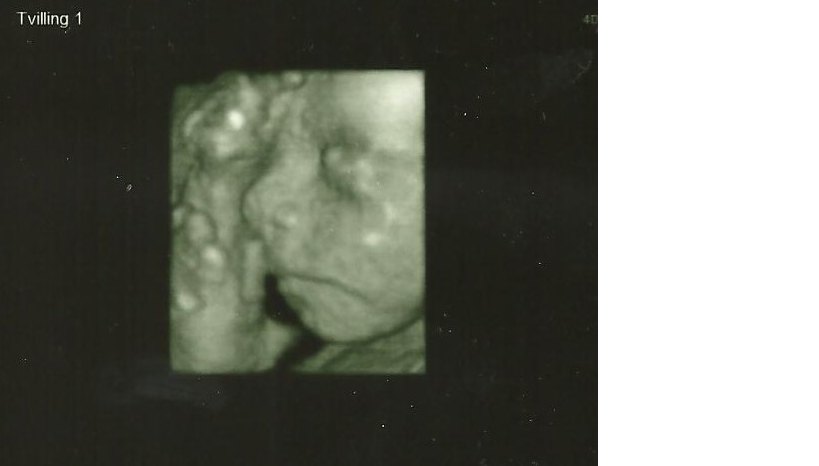

13+1 tvillinge a/lillepigen/Anastasia